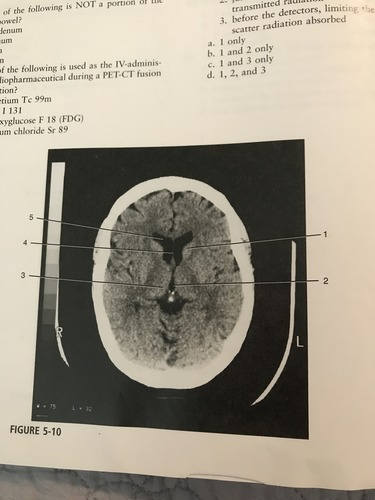

Which number corresponds to the anterior horn of the lateral ventricle

A) 1

B) 5

C) 3

D) 2

Number 3 on the figure corresponds to?

A) caudate nucleus

B) thalamus

C) third ventricle

D) pineal gland

Which number on the figure corresponds to the septum pellucidum?

A) 2

B) 3

C) 4

D) 5

C)4